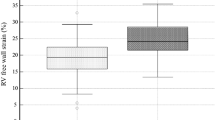

Comparison of echocardiographic parameters for patients with GLS < 18% and ≥18%

The relative wall thickness, LV mass index, and LV volumes of patients with GLS < 18% were significantly larger than those of patients with GLS ≥ 18%. In addition, LVEF of patients with GLS < 18% was significantly lower, and E/E’ for patients with GLS < 18% was significantly higher than those of patients with GLS ≥ 18%. Finally, the left atrial volume index (LAVI) for patients with GLS < 18% tended to be larger, but the difference was not statistically significant.